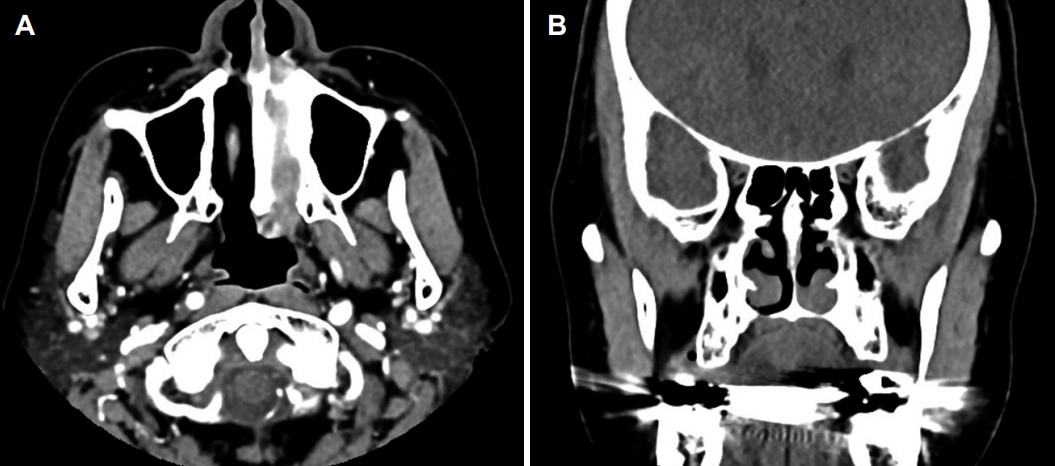

종물을 감별하기 위해 펀치 생검(punch biopsy), 부비동 전산화단층촬영(computed tomography, CT) 및 자기공명영상(magnetic resonance image, MRI)을 시행하였다. 펀치 생검의 결과는 다수의 급·만성 염증 세포가 존재하는 것으로 보고되었다. CT 영상에서 좌측 하비도의 점막비후가 관찰되었으며, 하비도 후방의 기저부에서 연조직 음영이 관찰되는 것 이외 주변의 골결손이나 양측 부비동 및 비강에 특이소견은 없었다(Fig. 2). MRI T2 조영 증강 영상에서는 좌측 하비갑개 후방에서 시작하여 후비공까지 차지하고 있는 종물이 강한 신호강도를 보였다(Fig. 3).

후비공 비용은 비내시경 검사에서 비강을 채우고 후비공까지 진행하는 비용 형태의 소견을 보이며, 영상의학적 검사는 비용의 기시부와 범위를 파악하고 감별 진단을 하는 데 도움이 된다. CT 영상에서 후비공 비용은 본 증례와 같이 비부비동에서 후비공까지 진행하는 저음영의 단일성 종물로 보이며[10], MRI 영상에서는 T1 강조영상에서 저신호강도, T2 강조영상에서 고신호강도 신호를 보여 악성 종양을 비롯한 비강에서 발생할 수 있는 단일성 질환의 감별에 도움이 된다[2]. 후비공 비용이 하비갑개에서 발생하는 경우는 매우 드물기 때문에 감별 진단으로 반드시 반전성 유두종(inverted papilloma)을 고려해야 하며[4,6], 그 외에도 비부비동염에 동반된 비용, 점액낭종(mucocele), 혈관섬유종(angiofibroma), 혈관종(hemangioma) 등 편측성 비부비동 내에서 종양으로 나타날 수 있는 질환들을 감별해야 한다[2,6]. 본 증례는 비내시경 및 영상검사에서 좌측 하비도의 후방에서 후비공까지 진행되는 종물이 확인되었지만, 종물의 경계가 지저분하고 종물의 발생 지점이 일반적이지 않아 처음에 후비공 비용을 고려하지 못하였다.

Fig. 1.Preoperative endoscopic findings. A bizarre single polypoid mass (*) is located between the left inferior turbinate and the basal floor of the nasal cavity. S: septum, IT: inferior turbinate. Fig. 2. Preoperative CT findings. Axial (A) and coronal (B) view. CT shows soft tissue density at the basal floor of the nasal cavity. Bone erosion is not observed and paranasal sinus is clear. Fig. 3.Preoperative MRI findings. Axial (A) and coronal (B) view. An ovoid homogenous enhancing mass (arrowhead) appears to originate from the posterior inferior side of the left inferior turbinate (arrow) and extends to the choana. Fig. 4. Operative findings. A pedicle (arrow) of single polypoid mass (*) is attached to the posterior side of the inferior turbinate. REFERENCES1. Lopatin A, Bykova V, Piskunov G. Choanal polyps: One entity, one surgical approach? Rhinology 1997;35(2):79-83.